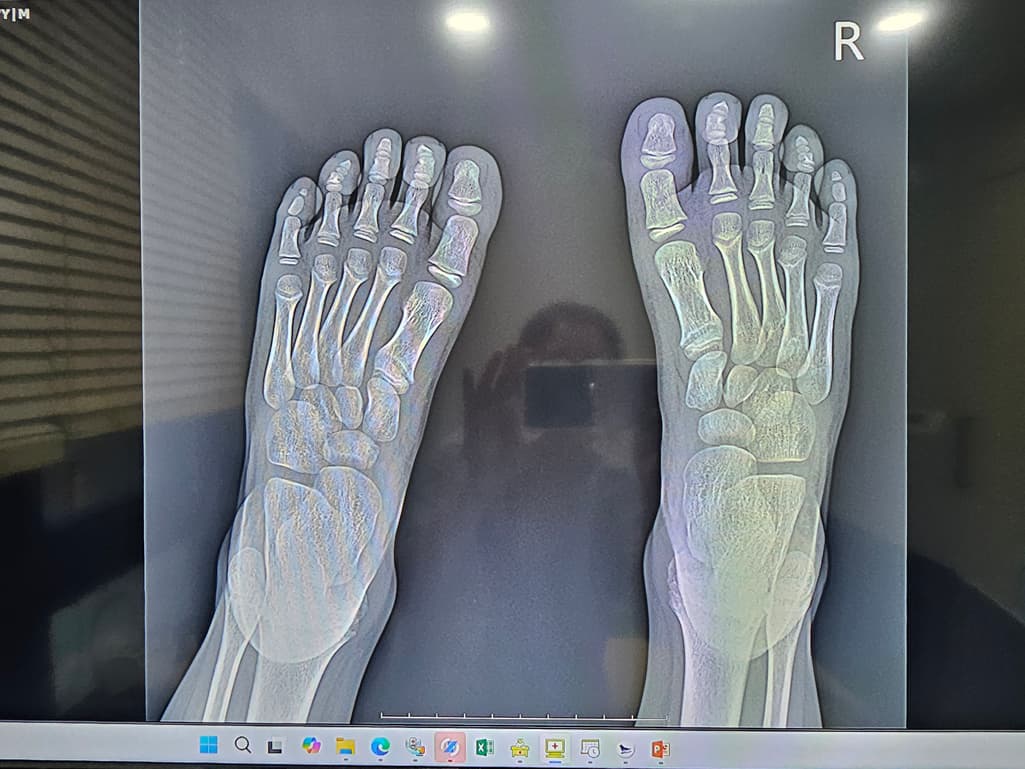

첫번째 사진은 엑스레이

8세남아 맨바닥에서 축구하다가 땅을 찼어요ㅠ